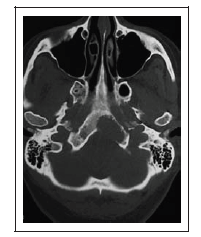

Uma mulher de 44 anos de idade passou a apresentar, na última semana, episódios esporádicos de parestesias em hemiface esquerda. Por duas vezes, apresentou dificuldade para ingerir líquidos. Apresentou três episódios de vertigens rotatórias e vômitos. De patologias pregressas, apenas hipertensão arterial leve, controlada com uso de losartana. O exame neurológico é normal. Não há alterações objetivas no exame nos nervos cranianos. Hemograma, glicemia, dosagem de derivados nitrogenados, eletrólitos no sangue: tudo normal. Exame de neuroimagem, reproduzido a seguir, mostra a presença de uma lesão expansiva osteolítica no terço inferior do clivus, à esquerda, que se estende até o arco anterior do atlas.